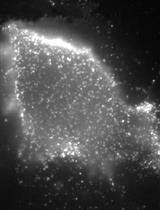

The subretinal layer between retinal pigment epithelium (RPE) and photoreceptors is a region involved in inflammation and angiogenesis during the procession of diseases such as age-related macular degeneration. The current protocols of whole mounts (retina and RPE) are unable to address the intact view of the subretinal layer because the separation between retina and RPE is required, and each separate tissue is then stained. Non-separate Sclerochoroid/RPE/Retina whole mount staining was recently developed and reported. The method can be further combined and optimized with melanin bleaching and tissue clearing. Here, we describe steps of both non-pigmented and pigmented mouse Sclerochoroid/RPE/Retina whole mount including eyeball preparation, staining, mounting and confocal scanning. In addition, we present the confocal images of RPE, subretinal microglia and the neighboring photoreceptors in Sclerochoroid/RPE/Retina whole mounts.

The retina in eyes is surrounded by retina pigmented epithelium (RPE), choroid and sclera. Generally, in whole mount staining, the retina tissue is separate from the choroid/RPE, and each part of the separate retina and choroid/RPE is stained. Thus, the separate whole mount staining of either retina or choroid/RPE does not address integral subretinal information. Recently, a Sclerochoroid/RPE/Retina whole mount protocol was developed (Kim et al., 2016; Ye et al., 2020). The method allows us to observe the integral and intact subretina as well as the neighboring RPE and photoreceptors. The method is also applicable to examine choroidal neovascularization from the choroid to the photoreceptor layer, but there is still a limitation in laser penetration depth of confocal microscopes, restraining the application of this protocol in animals with large eyes, which could be countered by use of light-sheet fluorescence microscope (Renier et al., 2014). Here, we illustrate the details of whole steps for immunofluorescent staining and mounting procedure of Sclerochoroid/RPE/Retina using mouse eyeballs.